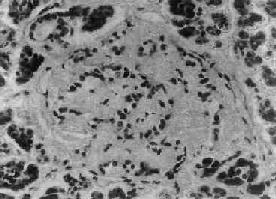

一、糖尿病糖尿病(diabetes mellitus)是由于胰岛素缺乏或(和)胰岛素的生物效应降低而引起的代谢障碍,为以持续的血糖升高和出现糖尿为主征的常见病,发病率为1%~2%。 【病因和发病机制】 糖尿病依病因可分为原发性及继发性两类。继发性糖尿病是由于炎症、肿瘤、手术等已知疾病造成胰岛广泛破坏,或由于其他内分泌的异常影响胰岛素的分泌所导致的糖尿病。日常所称糖尿病乃指原发性糖尿病,按其病因、发病机制、病变、临床表现及预后的不同可分为以下两种。 (一)胰岛素依赖型糖尿病 胰鸟素依赖型糖尿病(insulin-dependent diabetes mellitus,IDDM)又称Ⅰ型糖尿病,占糖尿病的10%~20%,患者多为青少年,发病时年龄小于20岁,胰岛B细胞明显减少,血中胰岛素明显降低,易合并酮血症甚至昏迷,治疗依赖胰岛素。目前认为其发病是在遗传易感性素质的基础上,胰岛感染了病毒(如腮腺炎病毒、风疹病毒及柯萨奇B4病毒等)或受毒性化学物质(如吡甲硝苯脲等)的影响,使胰岛B细胞损伤,释放出致敏蛋白,引起自身免疫反应(包括细胞免疫及体液免疫),导致胰岛的自身免疫性炎症,进一步引起胰岛B细胞严重破坏。 遗传易感性素质的主要根据是:一卵性双生的一方得病,50%的另一方也得病;与HLA类型有明显关系,在中国此型患者中DR3及DR4的分布频率明显增加,有人统计HLA-DR3或DR4的人群患此病的危险性比其他人高5~7倍。这些人存在免疫缺陷,一方面对病毒的抵抗力降低,另一方面抑制性T细胞的功能低下,易发生自身免疫反应(参阅本章毒性甲状腺肿)。 自身免疫反应的主要根据是:患者早期胰岛中有大量淋巴细胞浸润(胰岛炎),其中包括CD4+T细胞,与Ⅰ型糖尿病动物模型所见一致,从Ⅰ型糖尿病动物中提取的CD4+T细胞转移给正常动物可引发该病;90%患者发病后一年内血中可查出抗胰岛细胞抗体;10%的患者同时患有其他自身免疫性疾病。 (二)非胰岛素依赖型糖尿病 非胰岛素依赖型糖尿病(non-insulin dependent diabetes mellitus,NIDDM)又称Ⅱ型糖尿病,发病年龄多在40岁以上,没有胰岛炎症,胰岛数目正常或轻度减少。血中胰岛素开始不降,甚至增高,无抗胰岛细胞抗体,无其他自身免疫反应的表现。本型虽然也有家族性,一卵性双生同时发病者达90%以上,但未发现与HLA基因有直接联系。其发病机制不如Ⅰ型糖尿病清楚,一般认为是与肥胖有关的胰岛素相对不足及组织对胰岛素不敏感(胰岛素抵抗)所致。 肥胖是本型发生的重要因素,患者85%以上明显肥胖,只要减少进食,降低体重,血糖就可下降,疾病就可得到控制。引起发病有两个重要环节:①胰岛素相对不足及分泌异常。长期高热量食物,刺激胰岛B细胞,引起高胰岛素血症,但与同样肥胖的非糖尿病者相比,血中胰岛素水平较低,因此胰岛素相对不足。此外对葡萄糖等刺激,胰岛素早期呈现延缓反应,说明胰岛B细胞本身也有缺陷。长期过度负荷可使胰岛B细胞衰竭,因此本病晚期可有胰岛素分泌绝对缺乏,不过远比Ⅰ型为轻。②组织胰岛素抵抗,脂肪细胞越大对胰岛素就越不敏感,脂肪细胞及肌细胞的胰岛素受体减少,故对胰岛素反应差,这是高胰岛素血症引起胰岛素受体负调节的表现;此外营养物质过剩的细胞还存在胰岛素受体后缺陷(defect of postreceptor signaling by insulin),使葡萄糖及氨基酸等不能通过细胞膜进入细胞内,事实上营养过剩的细胞(也包括肝细胞及肌细胞)已失去正常处理血液中营养物质的能力。 非肥胖型Ⅱ型糖尿病患者对葡萄糖早期胰岛素反应比肥胖型患者更差,提示胰岛B细胞缺陷更严重,同时组织也呈胰岛素抵抗,其原因不明,可能与基因异常有关。 糖尿病患者在临床上不仅呈糖代谢障碍,也有脂肪及蛋白代谢障碍。胰岛素的不足(绝对或相对)及组织胰岛素抵抗使葡萄糖利用及糖原合成减少,导致高血糖。血糖超过肾阈值则出现尿糖及高渗性利尿(多尿)。这将引起水及电解质的丢失,进一步导致细胞内水减少,故患者出现口渴。由于营养物质得不到利用,患者食欲常增强,而体重却减轻(主要见于Ⅰ型及严重的Ⅱ型糖尿病)。 在胰岛素严重缺乏情况下(见于Ⅰ型糖尿病),蛋白及脂肪分解代谢增强而生成氨基酸及脂肪酸,氨基酸在肝内作为糖异生的原料被利用,而脂肪酸则在肝内氧化生成酮体(乙酰乙酸、β-羟丁酸及丙酮),出现酮血症(ketonemia)及酮尿症(ketonuria),前者可导致糖尿病昏迷。部分患者胰岛A细胞分泌的高血糖素(glucagon)增高,能加速脂肪酸的氧化。 【病理变化】 1.胰岛的病变不同类型的糖尿病及其不同时期,病变差异甚大。Ⅰ型糖尿病早期可见胰岛炎,胰岛内及其周围有大量淋巴细胞浸润,偶见嗜酸性粒细胞。胰岛细胞进行性破坏、消失,胰岛内A细胞相对增多,进而胰岛变小,数目也减少,有的胰岛纤维化;Ⅱ型糖尿病用常规方法检查时,早期几无变化,以后可见胰岛B细胞有所减少。常见变化为胰岛淀粉样变,在B细胞周围及毛细血管间有淀粉样物质沉着(图15-18),该物质可能是胰岛素B链的分解产物。

图15-18 糖尿病之胰岛 图示胰岛淀粉样变 2.其他组织变化及合并症 (1)动脉病变:①动脉粥样硬化,比非糖尿病患者出现较早且较严重;②细动脉玻璃样变,表现为基底膜增厚,富于Ⅳ型胶原的物质沉着,由于通透性增高致蛋白质漏出增多,故动脉壁有蛋白质沉积,造成管腔狭窄,引起组织缺血。合并高血压者,此变化更明显。 (2)肾病变:①肾小球硬化,有两种类型,一种是弥漫性肾小球硬化(diffuse glomerulosclerosis),肾小球毛细血管基底膜弥漫增厚,血管系膜细胞增生及基质增多;另一种为结节性肾小球硬化(nodular glomerulosclerosis),其特点是部分系膜轴有多量透明物质沉着,形成结节状,结节外周为毛细血管袢。②动脉硬化及小动脉硬化性肾硬化。③急性和慢性肾盂肾炎,易伴有肾乳头坏死,后者是由于在缺血的基础上对细菌感染更加敏感。④肾近曲小管远端上皮细胞有糖原沉积。 (3)糖尿病性视网膜病。可分两种,一种是背景性视网膜病(background retinopathy),视网膜毛细血管基底膜增厚,小静脉扩张,常有小血管瘤形成,继而有水肿、出血;另一种是由于血管病变造成视网膜缺氧,刺激引起血管新生及纤维组织增生,称为增殖性视网膜病(proliferative retinopathy)。视网膜病变易引起失明。除视网膜病变外,糖尿病易合并白内障。 (4)神经系统病变:周围神经包括运动神经、感觉神经和植物神经都可因血管变化引起缺血性损伤,出现各种症状,如肢体疼痛、麻木、感觉丧失、肌肉麻痹以致足下垂、腕下垂、胃肠及膀胱功能障碍等;脑细胞也可发生广泛变性。 (5)其他器官病变:肝细胞核内糖原沉积;由于高血脂症皮肤可出现黄色瘤结节或斑块。 (6)糖尿病性昏迷:其原因有①酮血症酸中毒;②高血糖引起脱水及高渗透压。 (7)感染:由于代谢障碍及血管病变使组织缺血,极易合并各种感染。